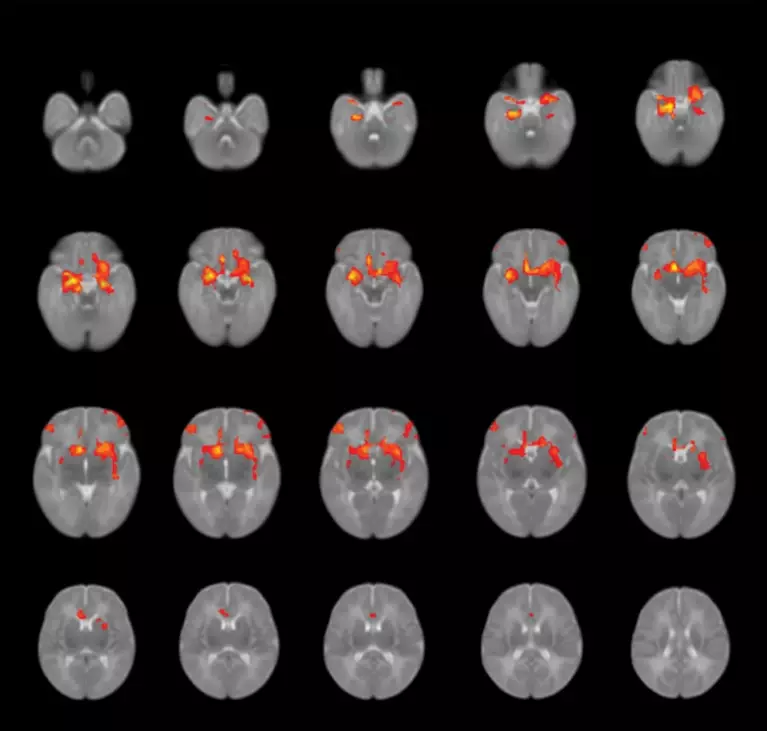

研究人员扫描了75名3个月大的婴儿大脑,发现,孕期存在焦虑或抑郁的孕妇,生出来的宝宝杏仁核和额前皮质结构均与对照组存在差异。